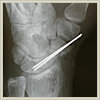

舟状骨偽関節:

術は、偽関節部の不要な組織を可能な限り掻爬(除去)してからピンで固定し、橈骨の一部を移植します。手術の後にギプスを約6週間行います。この方法で現在までほぼ100%の割合で舟状骨の偽関節部は骨癒合し、非常によい結果が得られています。